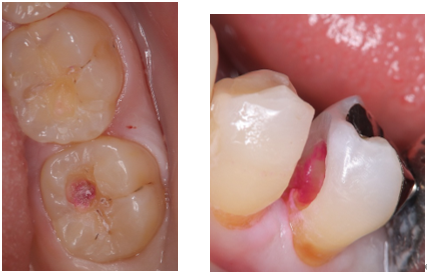

今回、虫歯治療に欠かせないアイテム・「う蝕検知液」・をご紹介します。

むし歯(う蝕)の治療では虫歯菌が入り込んだ歯質(感染歯質)のみを全部取り、むし歯菌が入っていない部分(健全な歯質)をしっかり残すことが必要です。

感染歯質は健全歯質に比べ柔らかく又変色もしているので、目視や削った感覚である程度はわかります。

ただしはっきりとその境目を見極めるのは困難です。

そこで「う蝕検知液」が必要になってきます。

この「う蝕検知液」は細菌に感染している歯質を染色して可視化してくれます。

それにより、感染歯質の取り残しを防ぎ、かつ健全歯質の削りすぎも防ぐことができるのです。

赤く染め出されたところが虫歯菌の入り込んでいる歯質(感染歯質) です。

この赤染部を除去してからプラスティックで「詰めもの」をしたり、型を取って「かぶせもの」をつくりします。